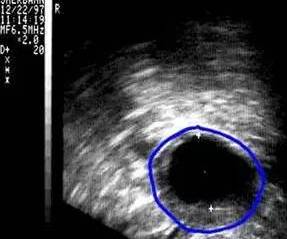

(图:排卵监测)

阴道B型超声动态监测卵泡的发育及排卵,是监测排卵最准确可靠的方法。通过阴道B超检查可以了解子宫及双侧附件(卵巢和输卵管)区的基本情况,测定卵巢内的窦卵泡计数,评估卵巢储备功能,动态监测排卵。